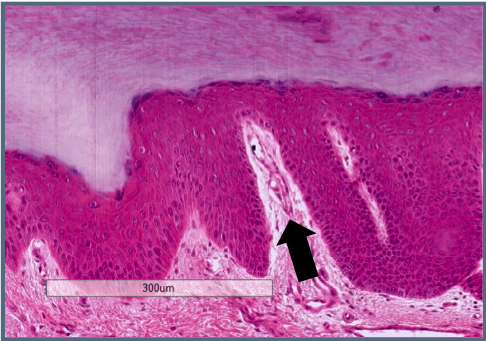

Give the name of this layer:

c. Papillary layer (paler area under the epithelium)

What statement describes best this structure? (Arrow)

b. Cross section of a duct

Classify this tissue (be specific):

d. Loose connective tissue (because it’s the papilary layer, very cellular)